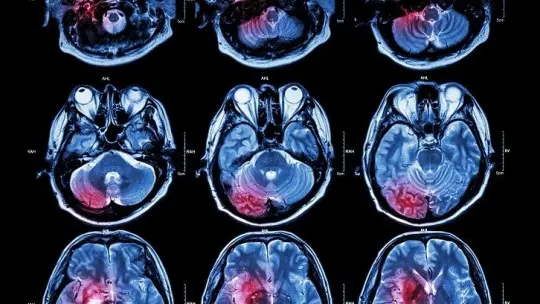

Neurologists rely heavily on imaging technologies that visualize brain structure and function. Magnetic resonance imaging (MRI) uses powerful magnetic fields and radio waves to create detailed pictures of brain anatomy, revealing tumors, stroke damage, areas of inflammation, tissue loss from degenerative disease, and structural abnormalities. Different MRI sequences provide different information—T1-weighted images show anatomy clearly, T2-weighted images highlight areas of abnormal fluid or inflammation, FLAIR sequences detect subtle white matter lesions, and diffusion-weighted imaging reveals acute stroke within hours of onset. Computed tomography (CT) scans use x-rays to quickly image the brain, making them ideal for emergency settings where rapid detection of bleeding, skull fractures, or large strokes is critical. Functional MRI (fMRI) measures brain activity by detecting blood flow changes, showing which brain regions activate during specific tasks. PET scans measure metabolic activity and can detect abnormal protein deposits like the amyloid plaques and tau tangles characteristic of Alzheimer’s disease. These imaging modalities allow neurologists to see what’s physically wrong inside the skull—where tissue is damaged, where inflammation exists, where tumors are growing, where blood vessels are blocked or bleeding.